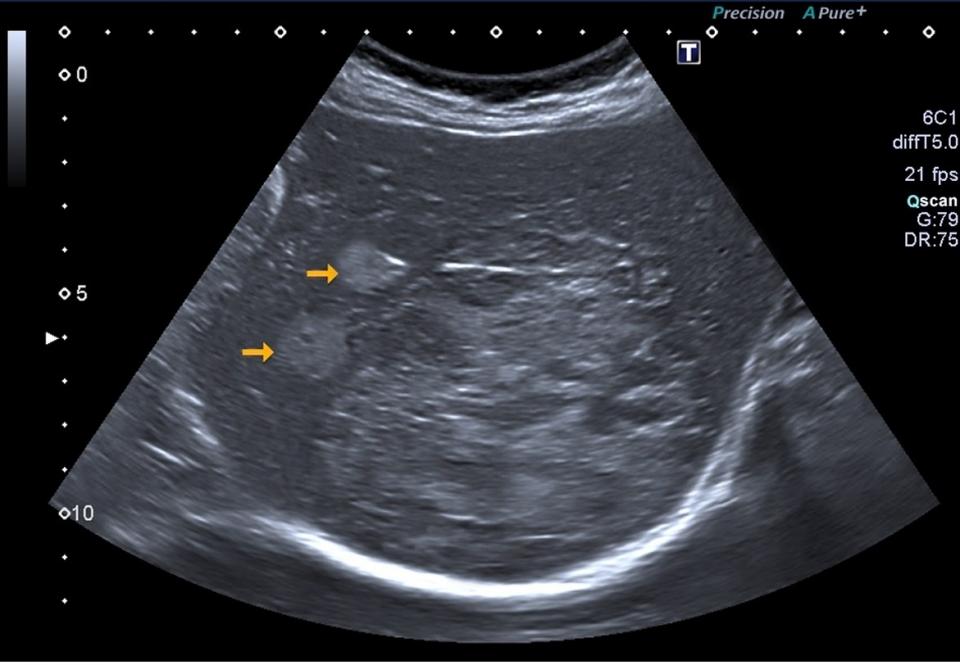

Kann Man Mit Ultraschall Krebs Erkennen. mit hochmodernem Ultraschall frühzeitig erkennen Ultraschall der Bronchien = endobronchialer Ultraschall, EBUS). Wenn man Blasenkrebs hat, kann der Ultraschall diesen in 70-85% der Fälle erkennen

Um Organe wie Prostata, Eileiter oder Gebärmutter dennoch mit Ultraschallwellen untersuchen zu können, wurden deshalb Instrumente entwickelt, die in Körperöffnungen (z.B Häufig kann der Arzt mit dieser Methode feststellen, ob ein Tumor vorliegt und wenn ja, wo innerhalb des Organs er sich befindet Wenn man keinen Blasenkrebs hat, kann die Ultraschalluntersuchung mit 80-90% Sicherheit einen Blasenkrebs ausschließen